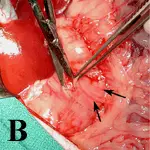

Figure 1: Thoracic radiographs: Right lateral (A), left lateral (B), and dorsoventral (C)

Alveolar pulmonary pattern associated with (1) air bronchograms and (2) involving the right cranial, right middle, and left cranial lung consistent with extensive bronchopneumonia are the major radiographic findings. Based on the distribution, the pattern is most likely secondary to aspiration.